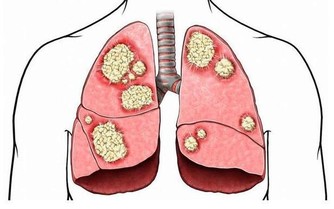

1. 綠茶如何防癌?

癌症的發生與自由基(Free Radicals)對細胞的損害密切相關,而綠茶中的**兒茶素(EGCG)**具有強大的抗氧化能力,可以幫助人體清除自由基,減少細胞突變的風險。

- 降低腫瘤生長:綠茶中的兒茶素可抑制癌細胞增殖,特別是在乳腺癌、前列腺癌、結腸癌方面,有一定保護作用。

- 減少發炎反應:慢性發炎是癌症發生的主要因素之一,綠茶能減少體內發炎指數,降低癌變風險。

- 幫助DNA修復:綠茶的多酚能夠減少DNA受損,防止基因突變導致的癌細胞生成。